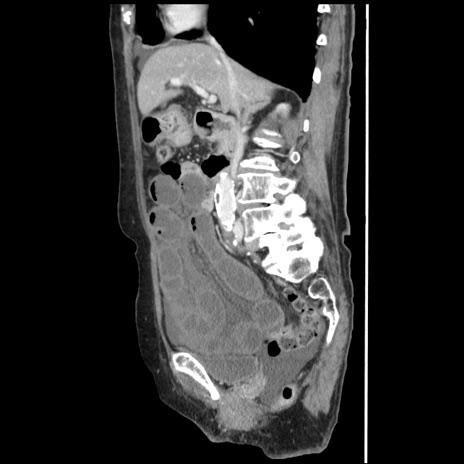

冠状断像

【症例】80歳代女性

【主訴】腹痛

【現病歴】8時間前から腹痛あり来院。

【既往歴】糖尿病、脂質異常症、子宮体癌にて子宮全摘術

【身体所見】意識清明・会話良好だが腹痛で苦悶様、全腹部にわたって反跳痛と圧痛あり

【データ】WBC 13600、CRP 0.14、LDH 224、CK 90